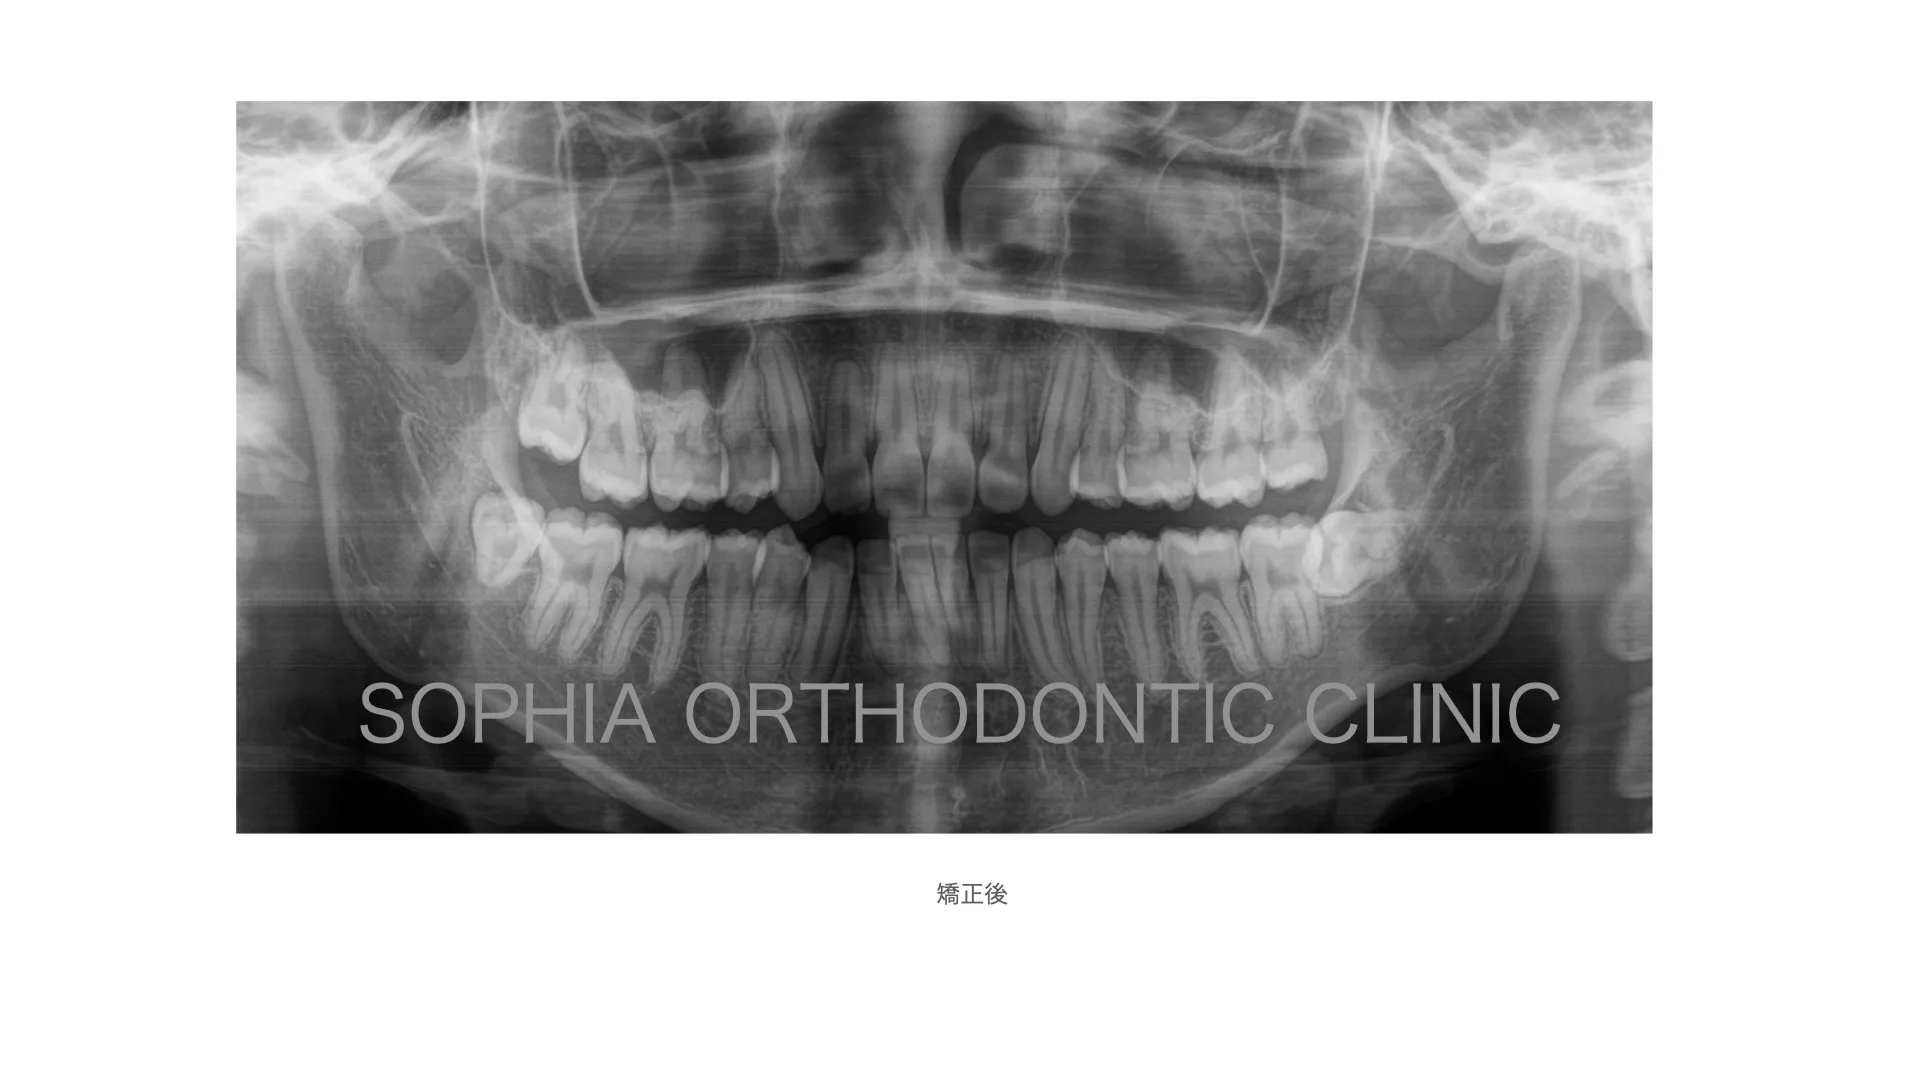

症例 上顎前突 抜歯